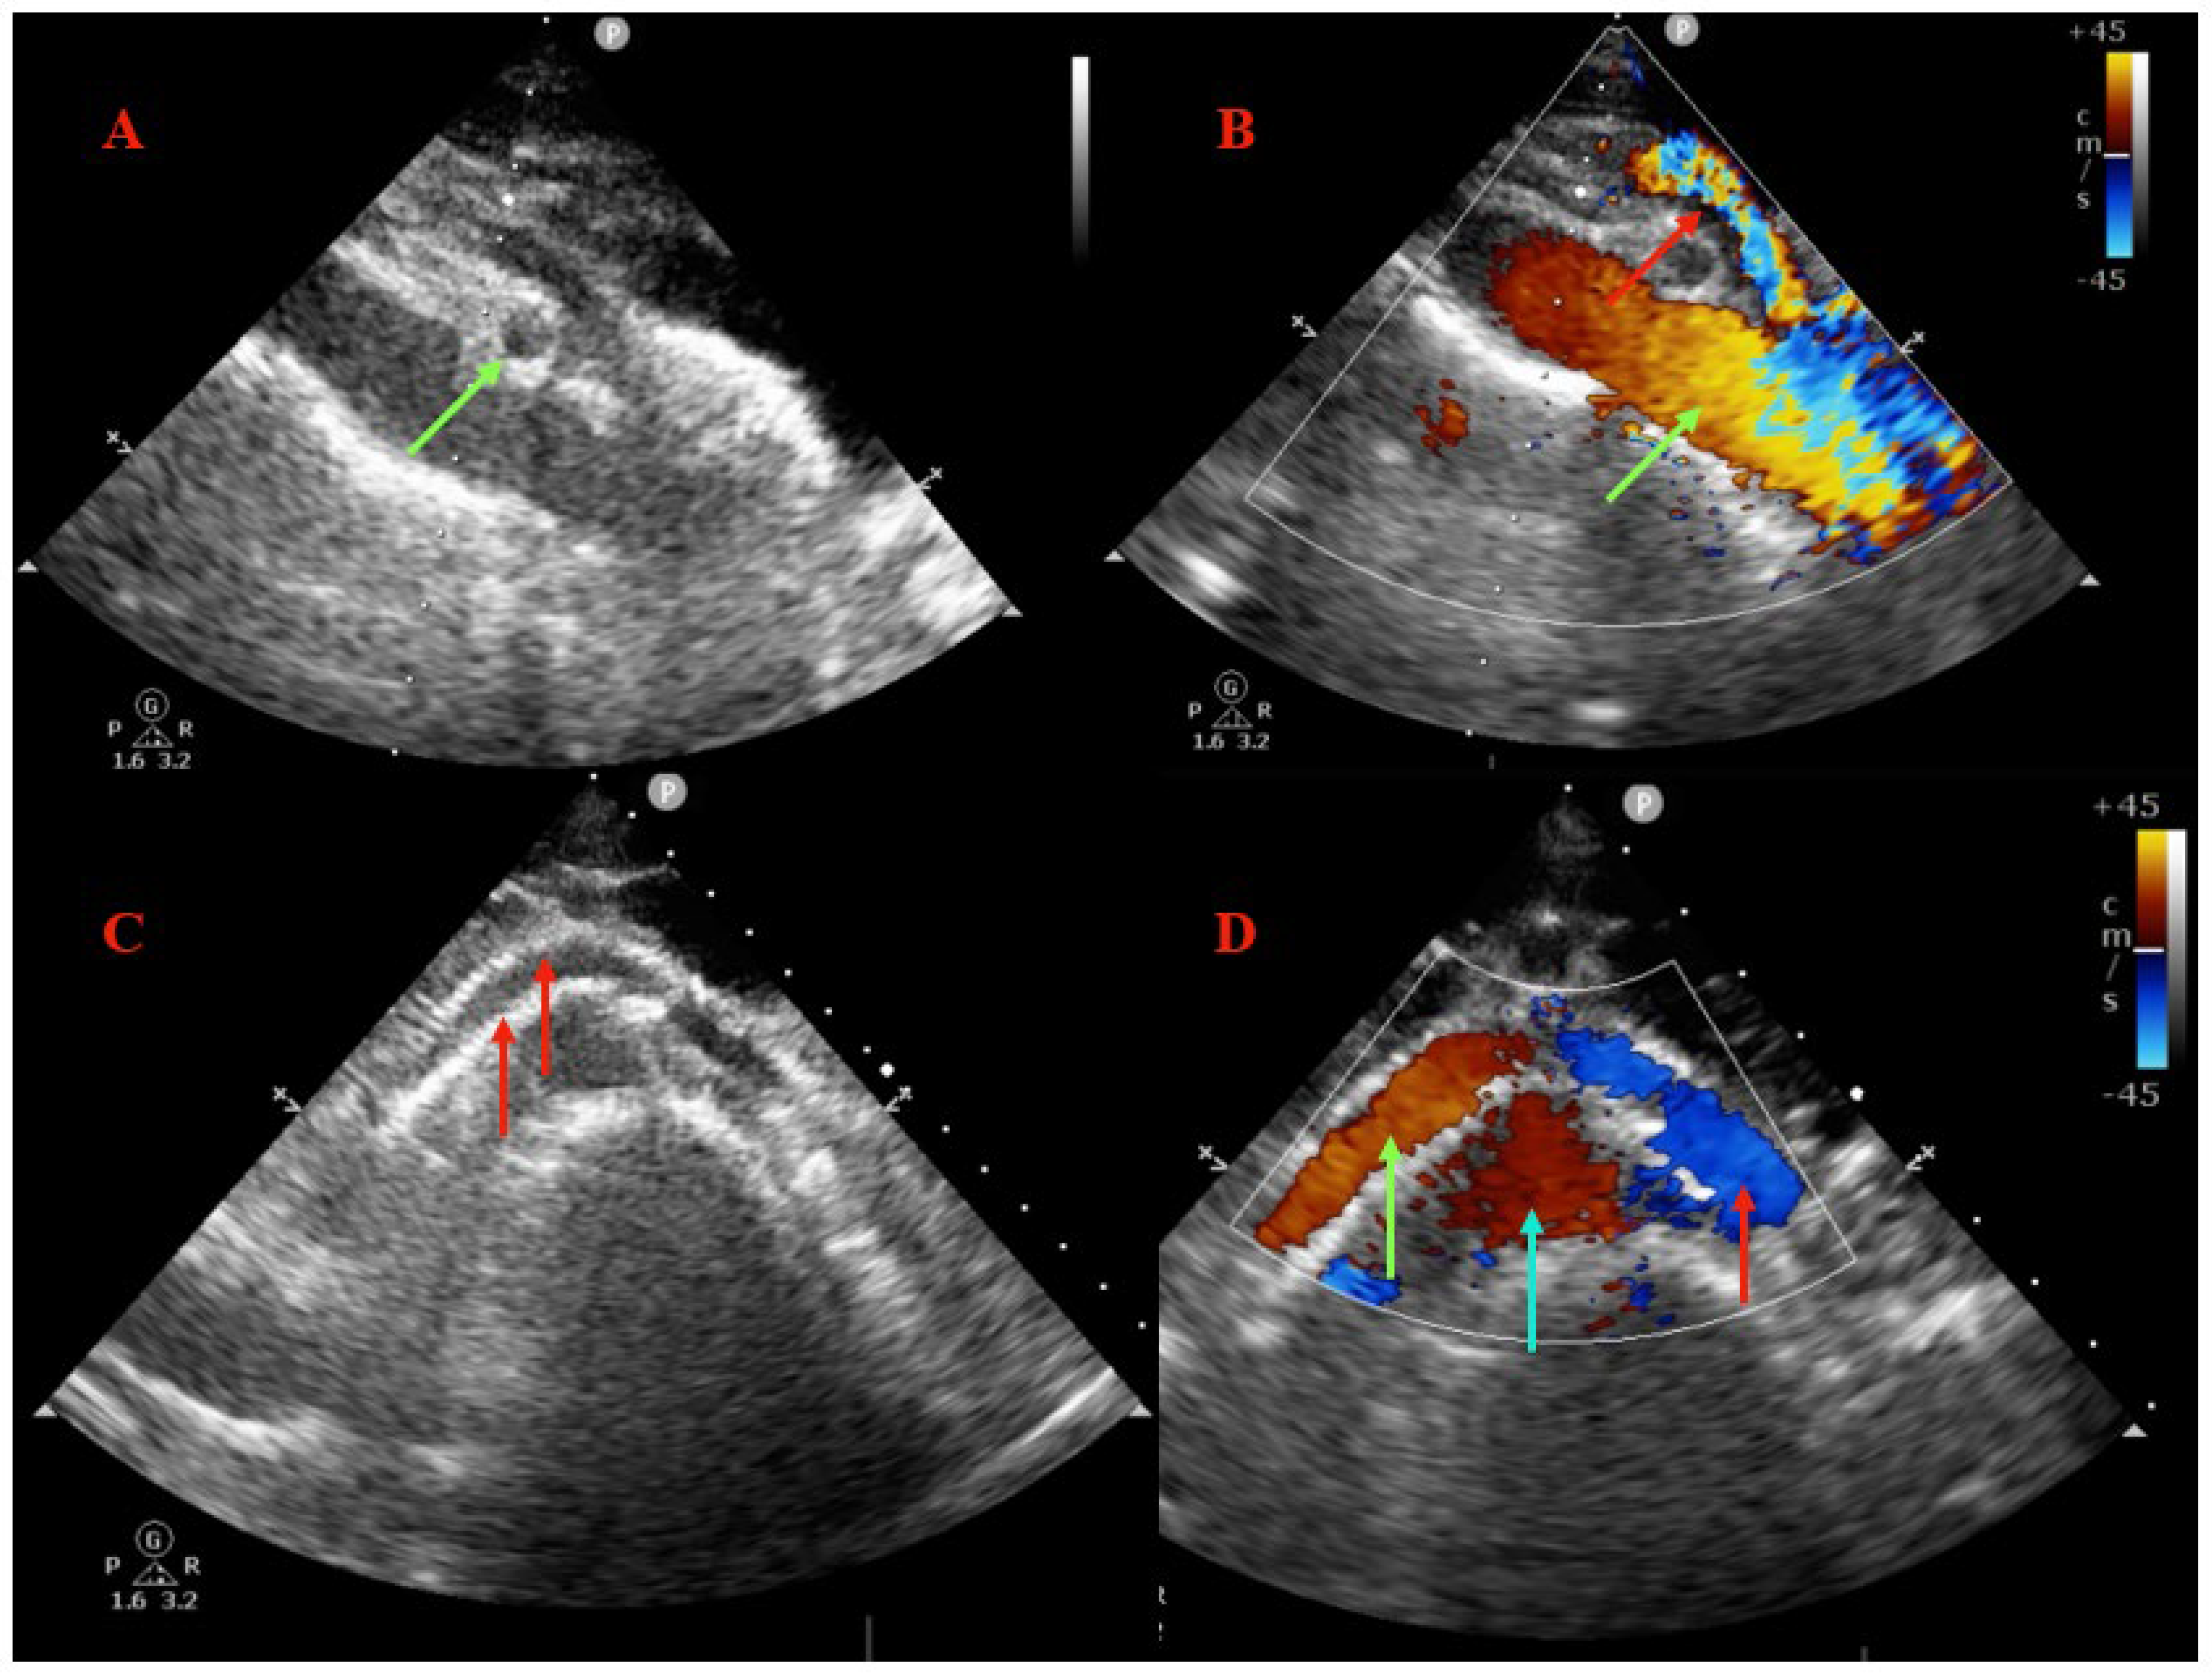

2. Imaging Diagnosis

3.1. Case Report